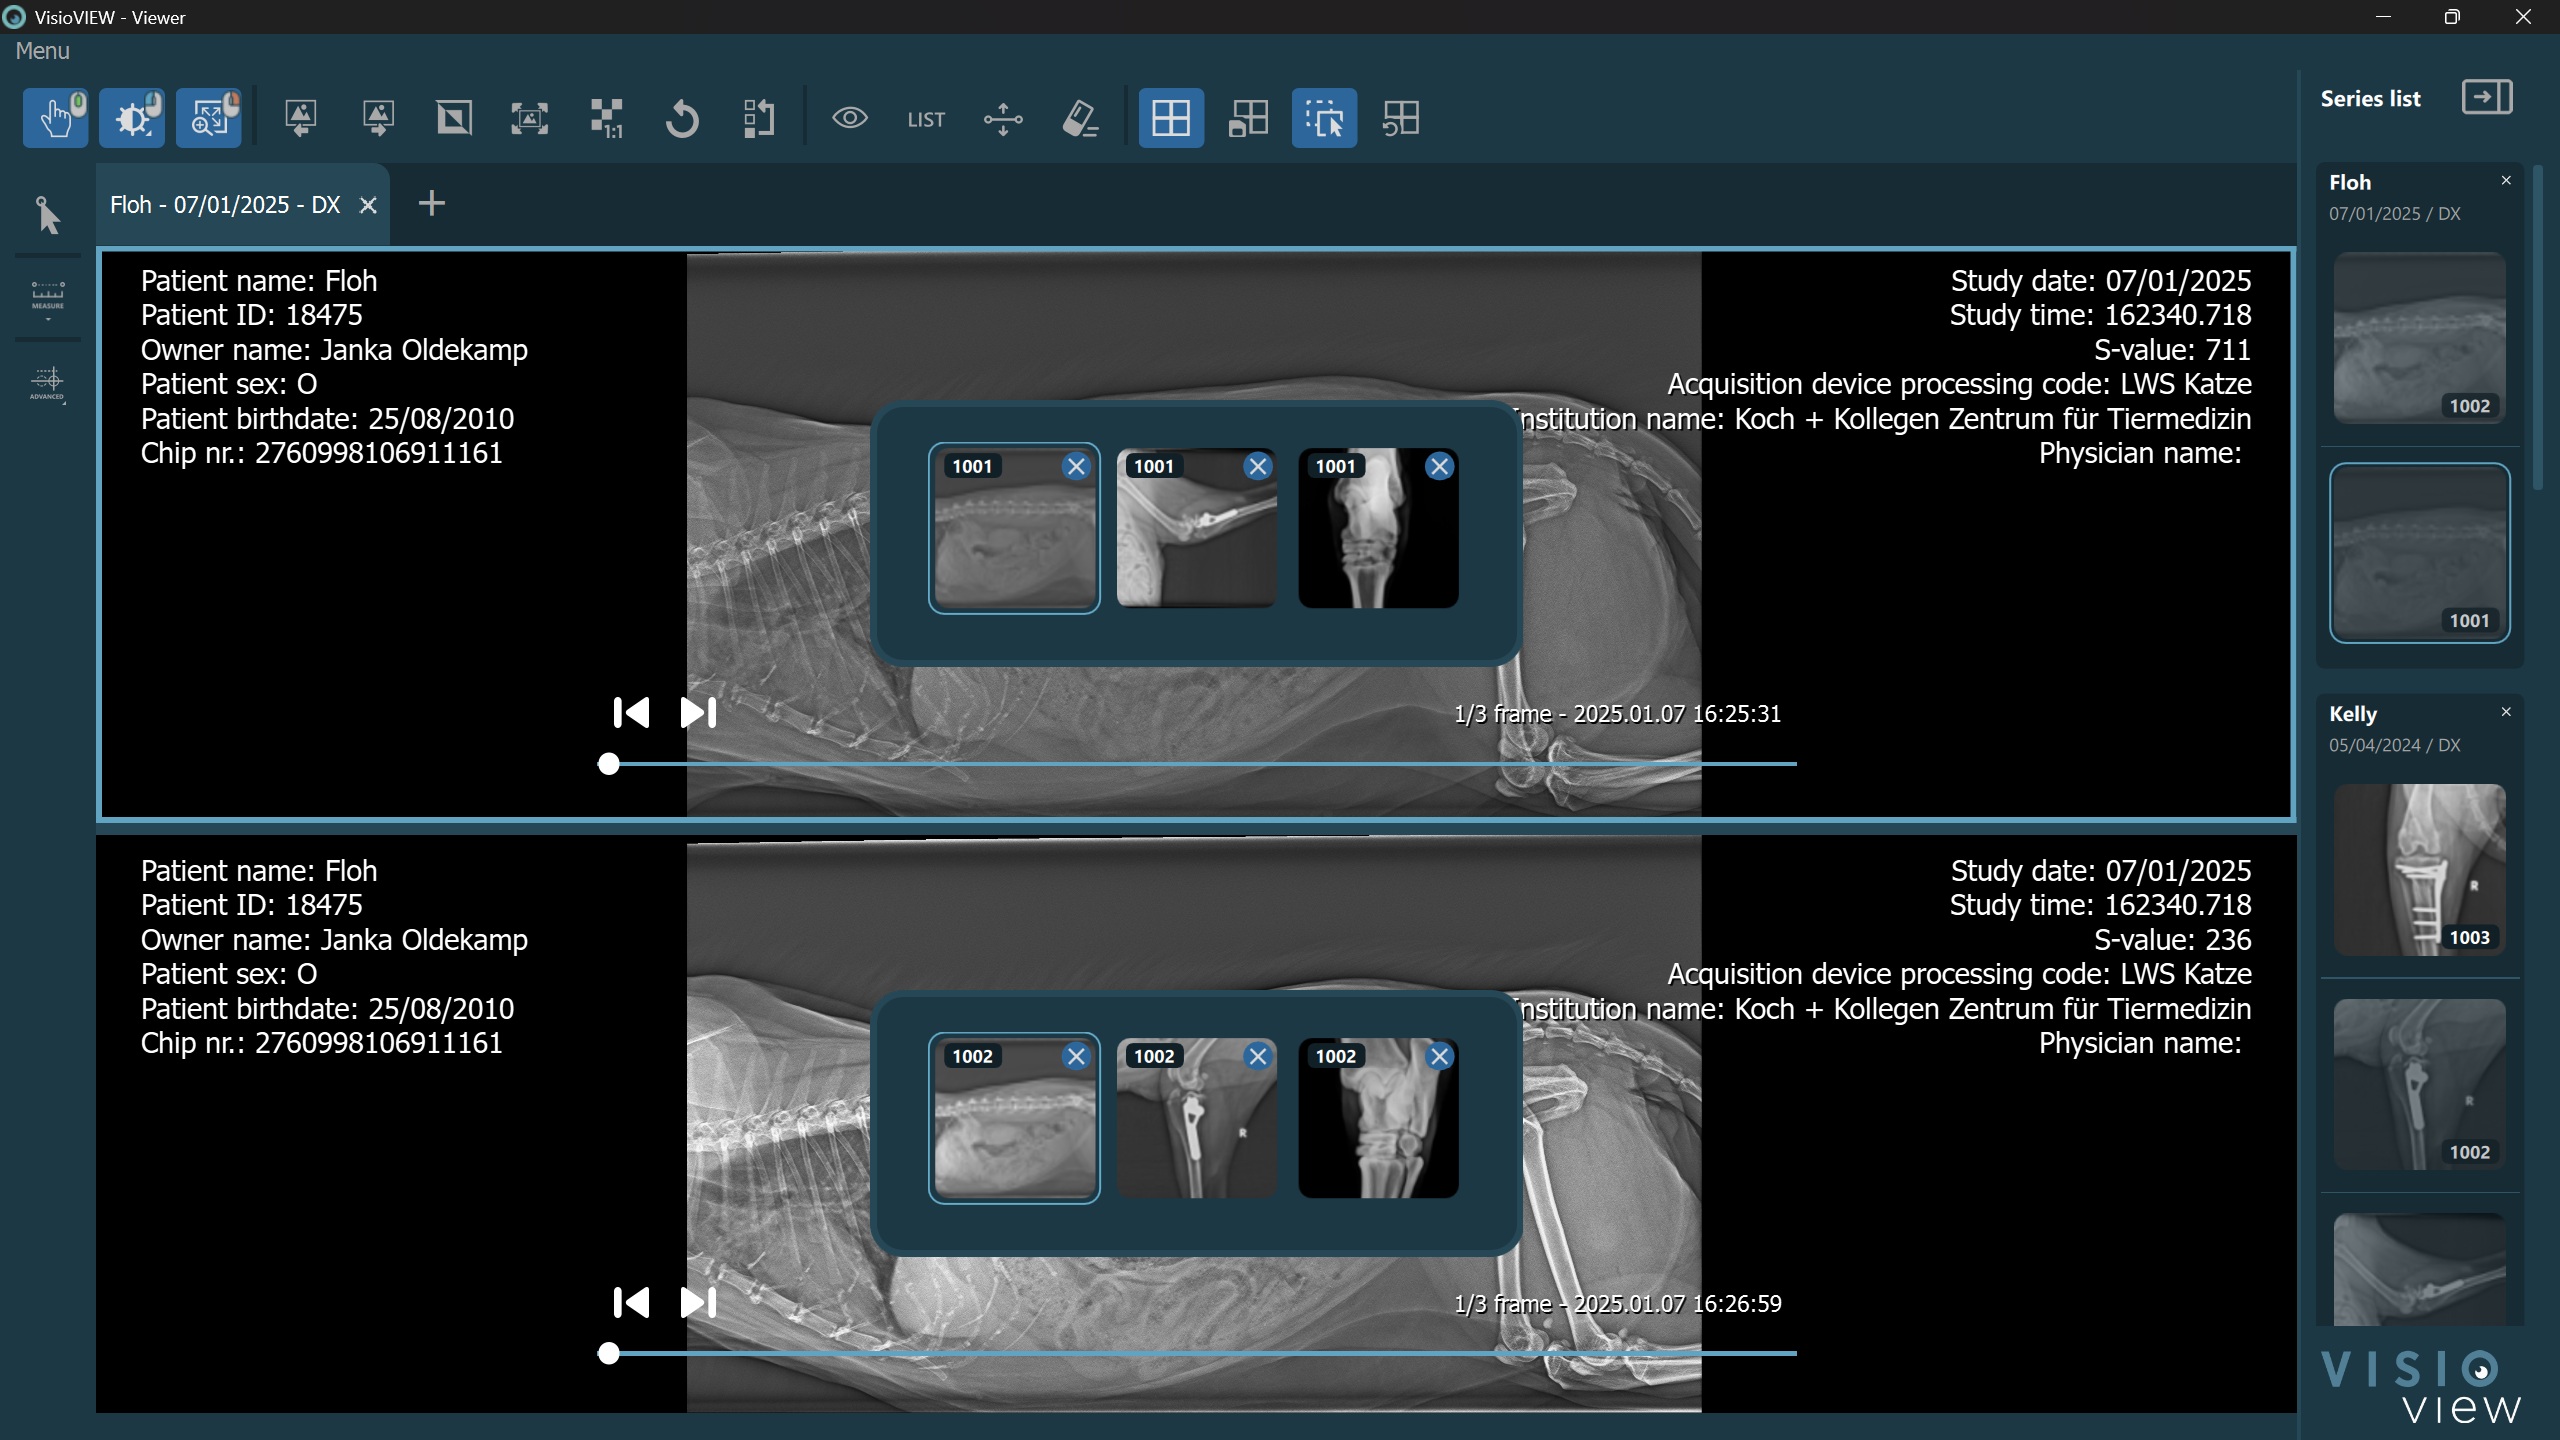

Open Viewer Image Stack¶

The VisioVIEW Viewer offers users the ability to stack multiple single-frame images inside one cell. This feature is also part of the Hanging Protocols, when multiple images share the same instance rules for a specific viewer cell.

To open the current image stacks of each cell, press the Open Viewer Image Stack button in the Viewer toolbar.

Users can drag and drop images from the series panel directly into an opened image stack, or drag and drop images from one stack into another. The images in the viewer stack are always ordered by the series date and time DICOM tags. The series number of each series is labeled in the top left corner of the preview representing the series.

Dropping an image directly into the cell completely discards the entire stack. Remove individual images from the stack by pressing the x button in the top right corner of each image.

More information on how the Viewer Image Stack is connected to the Viewer Series Panel is available in the following section.